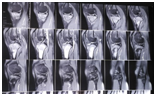

Magnetic resonance imaging (MRI) showed that a mass occupied the same part of the left tibia (6 cm and 3.5 cm and 3.0 cm in diameter) where sclerosis was seen on the radiograph, and that soft tissues around the lesion were edematous (Figure 2). Bone scintigraphy showed an abnormal uptake on the proximal part of the left tibia. Pulmonary CT was normal.

Figure 2 MR images of the left knee showing extent of growth and tissue oedema.